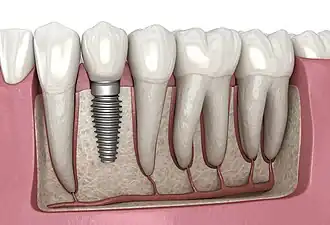

A dental implant (also known as an endosseous implant or fixture) is a prosthesis that interfaces with the bone of the jaw or skull to support a dental prosthesis such as a crown, bridge, denture, or facial prosthesis or to act as an orthodontic anchor. The basis for modern dental implants is a biological process called osseointegration, in which materials such as titanium or zirconia form an intimate bond to the bone.[1] The implant fixture is first placed so that it is likely to osseointegrate, then a dental prosthetic is added. A variable amount of healing time is required for osseointegration before either the dental prosthetic (a tooth, bridge, or denture) is attached to the implant or an abutment is placed which will hold a dental prosthetic or crown.

The primary use of dental implants is to support dental prosthetics (i.e. false teeth). Modern dental implants work through a biologic process where bone fuses tightly to the surface of specific materials such as titanium and some ceramics. The integration of implant and bone can support physical loads for decades without failure.[21]: 103–107

Single tooth implant restoration

Single tooth restorations are individual freestanding units not connected to other teeth or implants, used to replace missing individual teeth.[23] For individual tooth replacement, an implant abutment is first secured to the implant with an abutment screw. A crown (the dental prosthesis) is then connected to the abutment with dental cement, a small screw, or fused with the abutment as one piece during fabrication.[28]: 211–232 Dental implants, in the same way, can also be used to retain a multiple tooth dental prosthesis either in the form of a fixed bridge or removable dentures.